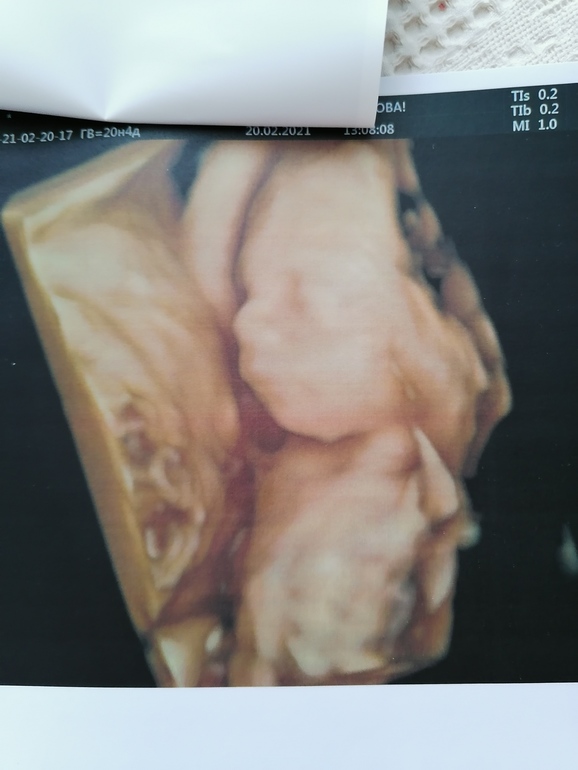

УЗИ прошло шикарно, врач меня вспомнила, все расспросила как и что. Всё рассмотрела идеально. Муж сидел с открытым ртом. Сделали нам аж 15 фото, прям фотосессия была у сыночка🥰😉. Он так мило зевал, язычком водичку ловил💙💙💙. Прям умиление сплошное🥰. Лежит головой вниз.

Ну и наши фоточки🥰👶🙏🙏🙏.

Ну и фотосессия сыночка👶🙏🙏🙏🥰.